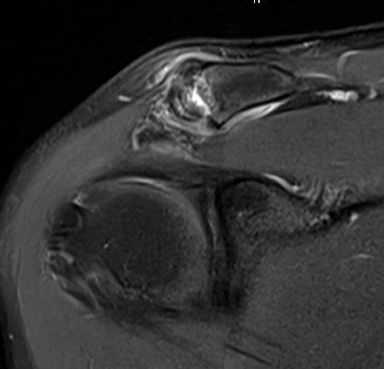

MRI

Acromioclavicular osteoarthritis

Stein et al. J Should Elbow Surg 2001

Grade I: Normal

Grade II: Capsular distension, bone marrow edema, mild joint narrowing

Grade III: Capsular distension, joint space narrowing, marginal osteophytes

Grade IV: Markedly abnormal ACJ with large osteophytes